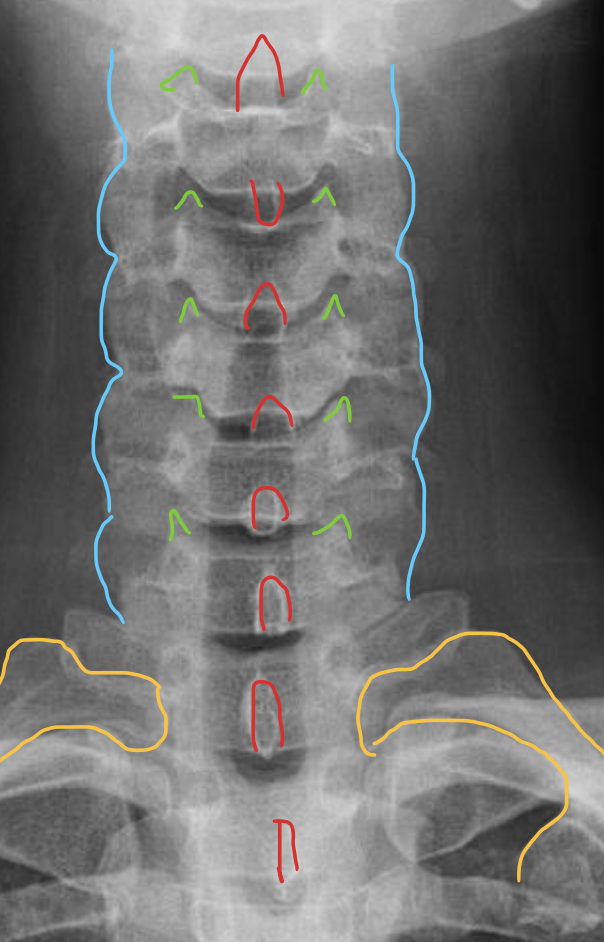

钩突

Uncinate process

关节柱 / 侧块

Articular pillars

棘突

Spinous process

1st rib